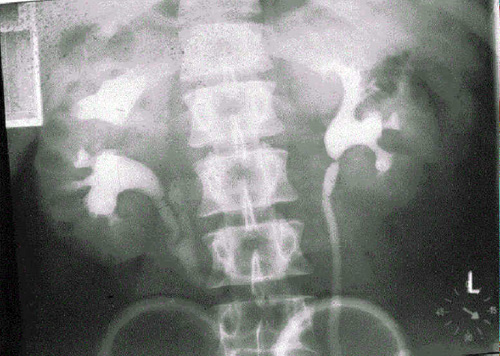

Пиелография

Внутривенная пиелография почек.